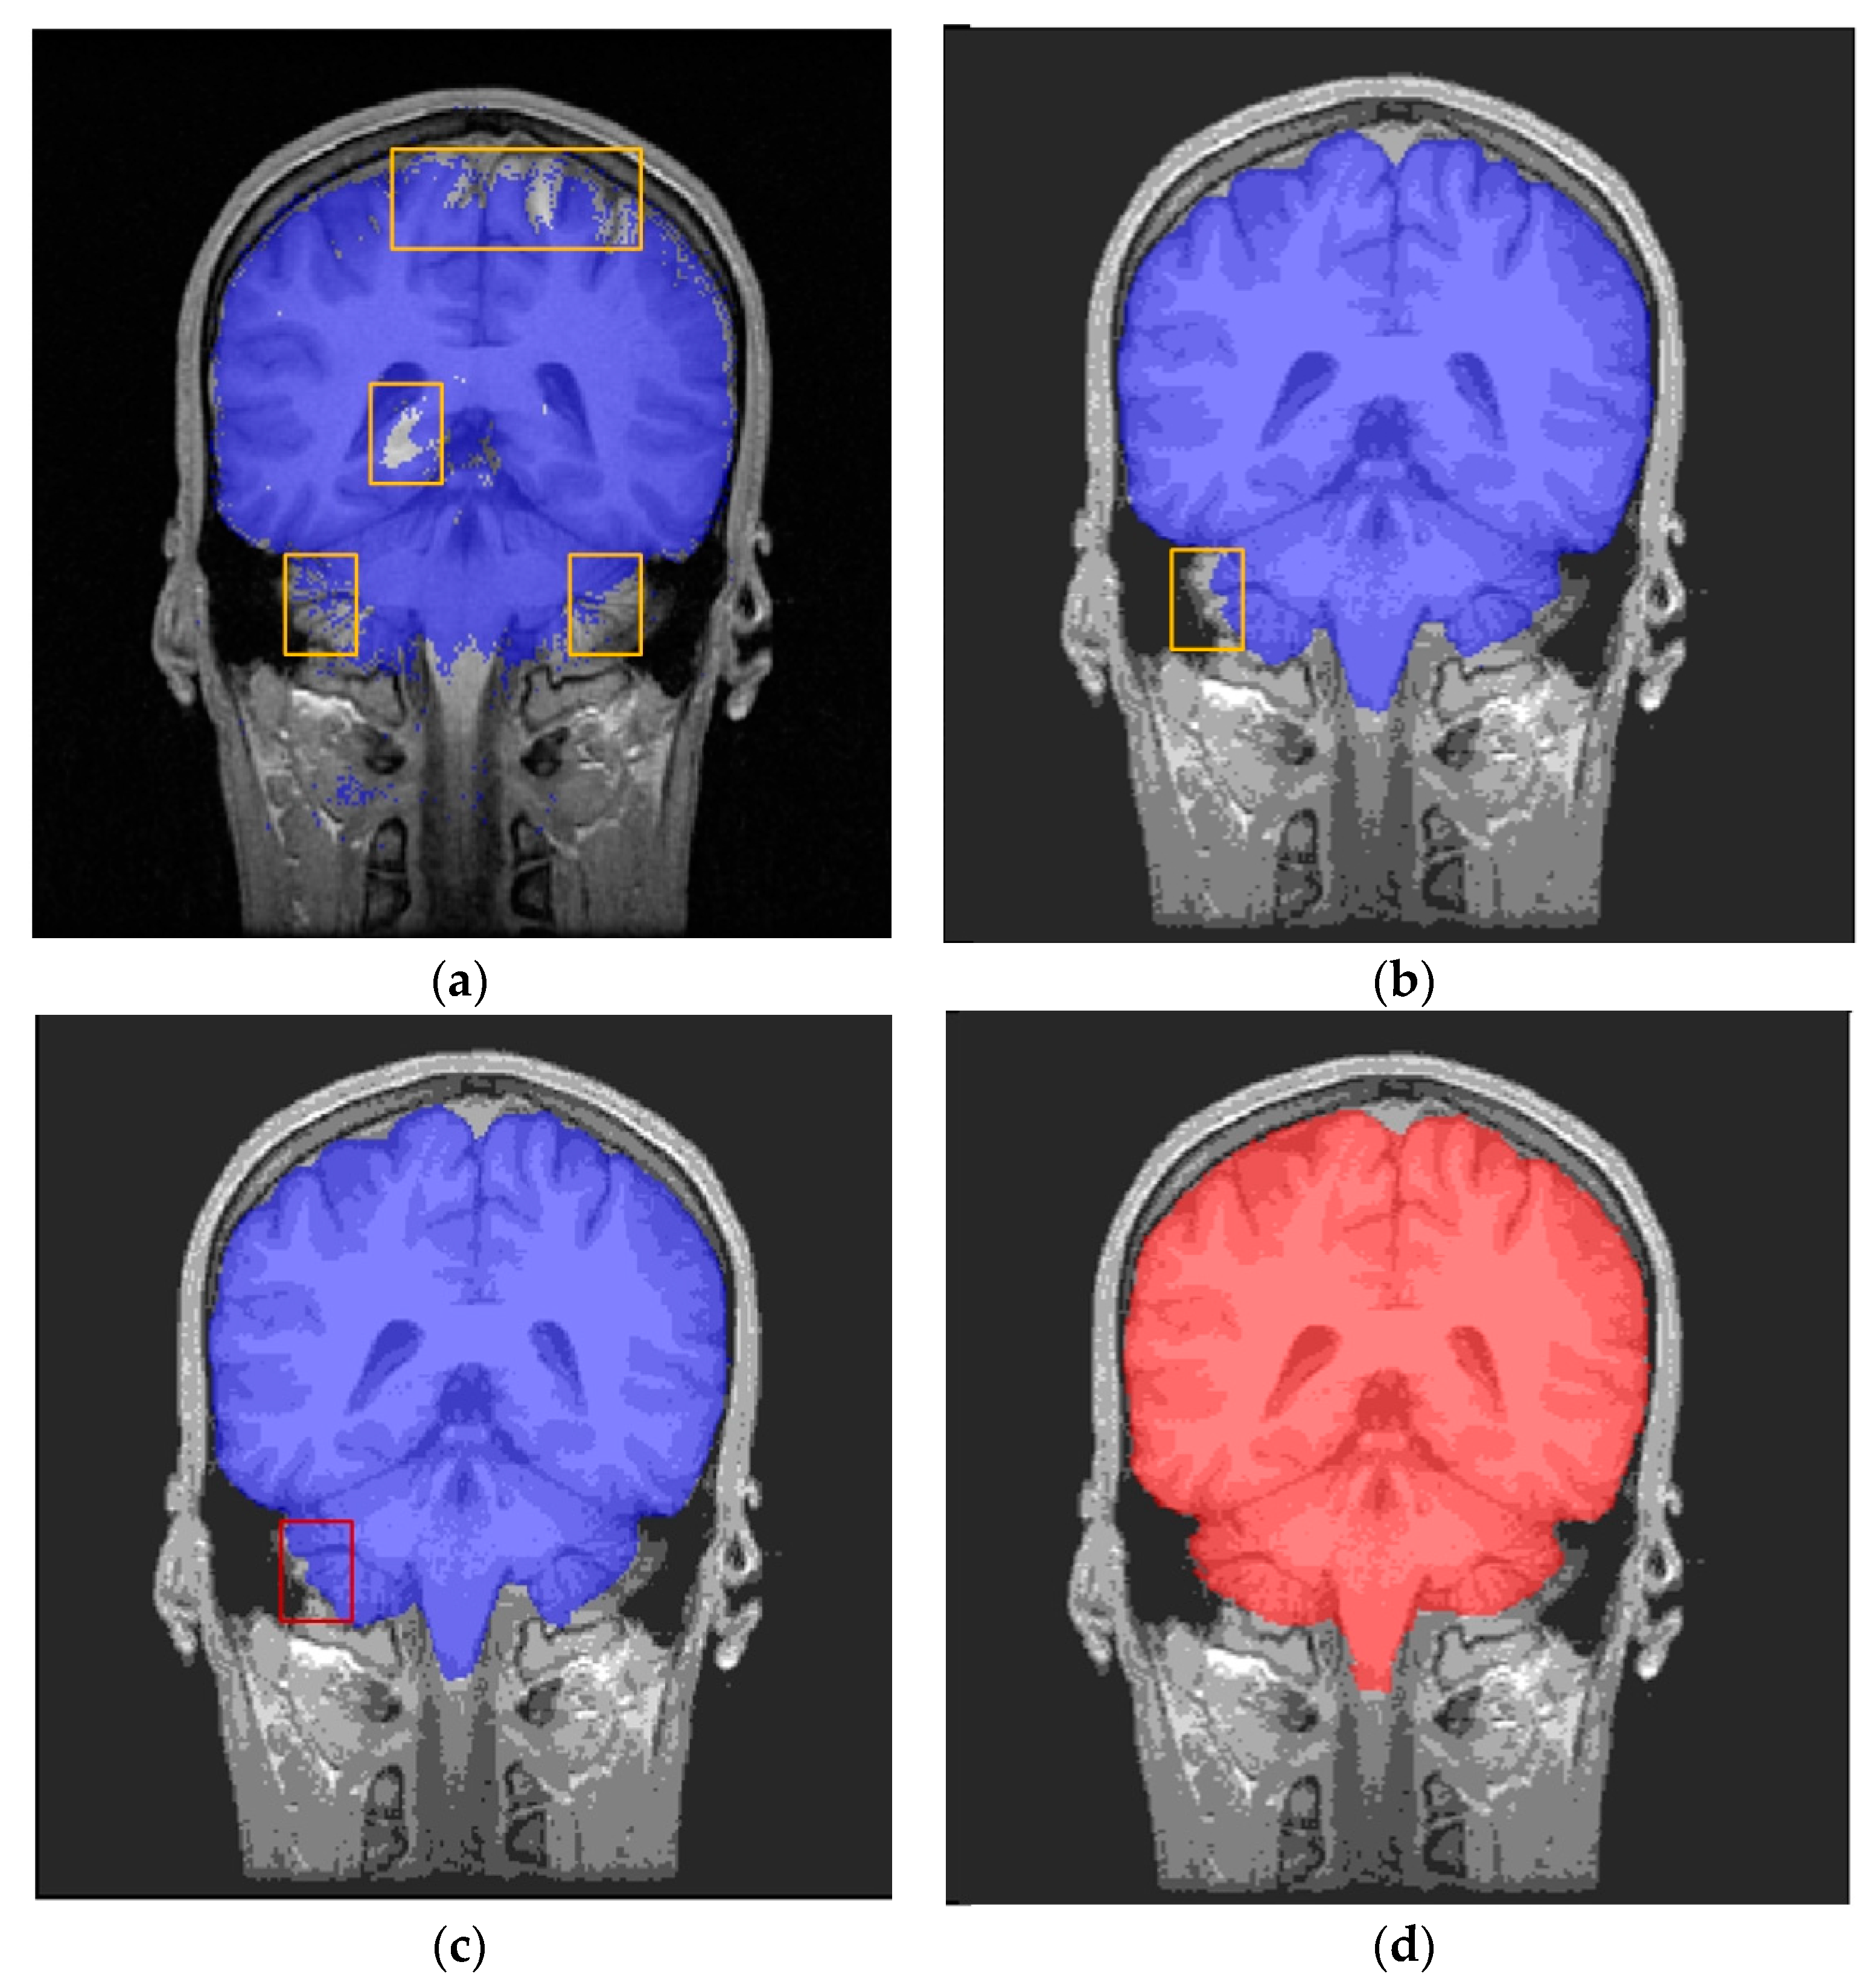

3.2. Results